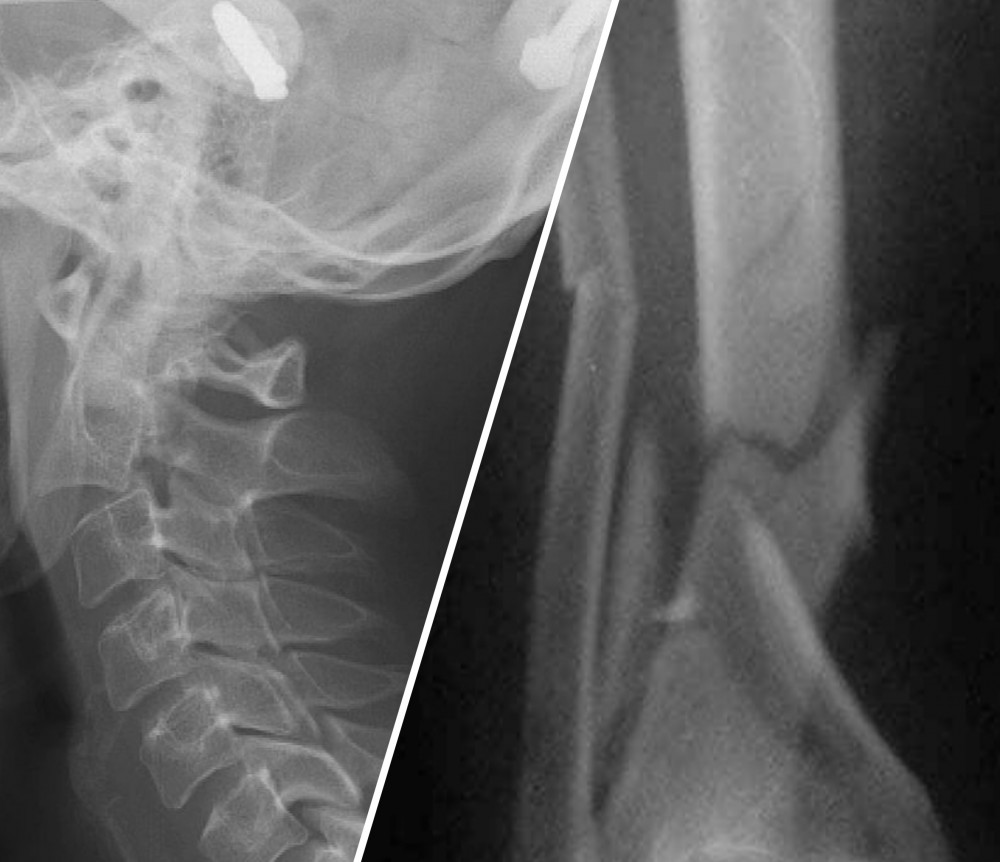

У мужчины перелом и сдвиг шейного отдела позвоночника, перелом голени и руки. Мужчину прооперировали но до сих пор не приходит в себя. Авторы: СОФЬЯ КАЛИНИЧЕНКО и ОЛЕГ ЧЕРДАНЦЕВ